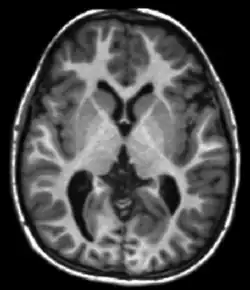

Diffusion weighted

DTI image

Diffusion MRI measures the diffusion of water molecules in biological tissues.[41] Clinically, diffusion MRI is useful for the diagnoses of conditions (e.g., stroke) or neurological disorders (e.g., multiple sclerosis), and helps better understand the connectivity of white matter axons in the central nervous system.[42] In an isotropic medium (inside a glass of water for example), water molecules naturally move randomly according to turbulence and Brownian motion. In biological tissues however, where the Reynolds number is low enough for laminar flow, the diffusion may be anisotropic. For example, a molecule inside the axon of a neuron has a low probability of crossing the myelin membrane. Therefore, the molecule moves principally along the axis of the neural fiber. If it is known that molecules in a particular voxel diffuse principally in one direction, the assumption can be made that the majority of the fibers in this area are parallel to that direction.

The recent development of diffusion tensor imaging (DTI)[43] enables diffusion to be measured in multiple directions, and the fractional anisotropy in each direction to be calculated for each voxel. This enables researchers to make brain maps of fiber directions to examine the connectivity of different regions in the brain (using tractography) or to examine areas of neural degeneration and demyelination in diseases like multiple sclerosis.

Another application of diffusion MRI is diffusion-weighted imaging (DWI). Following an ischemic stroke, DWI is highly sensitive to the changes occurring in the lesion.[44] It is speculated that increases in restriction (barriers) to water diffusion, as a result of cytotoxic edema (cellular swelling), is responsible for the increase in signal on a DWI scan. The DWI enhancement appears within 5–10 minutes of the onset of stroke symptoms (as compared to computed tomography, which often does not detect changes of acute infarct for up to 4–6 hours) and remains for up to two weeks. Coupled with imaging of cerebral perfusion, researchers can highlight regions of "perfusion/diffusion mismatch" that may indicate regions capable of salvage by reperfusion therapy.